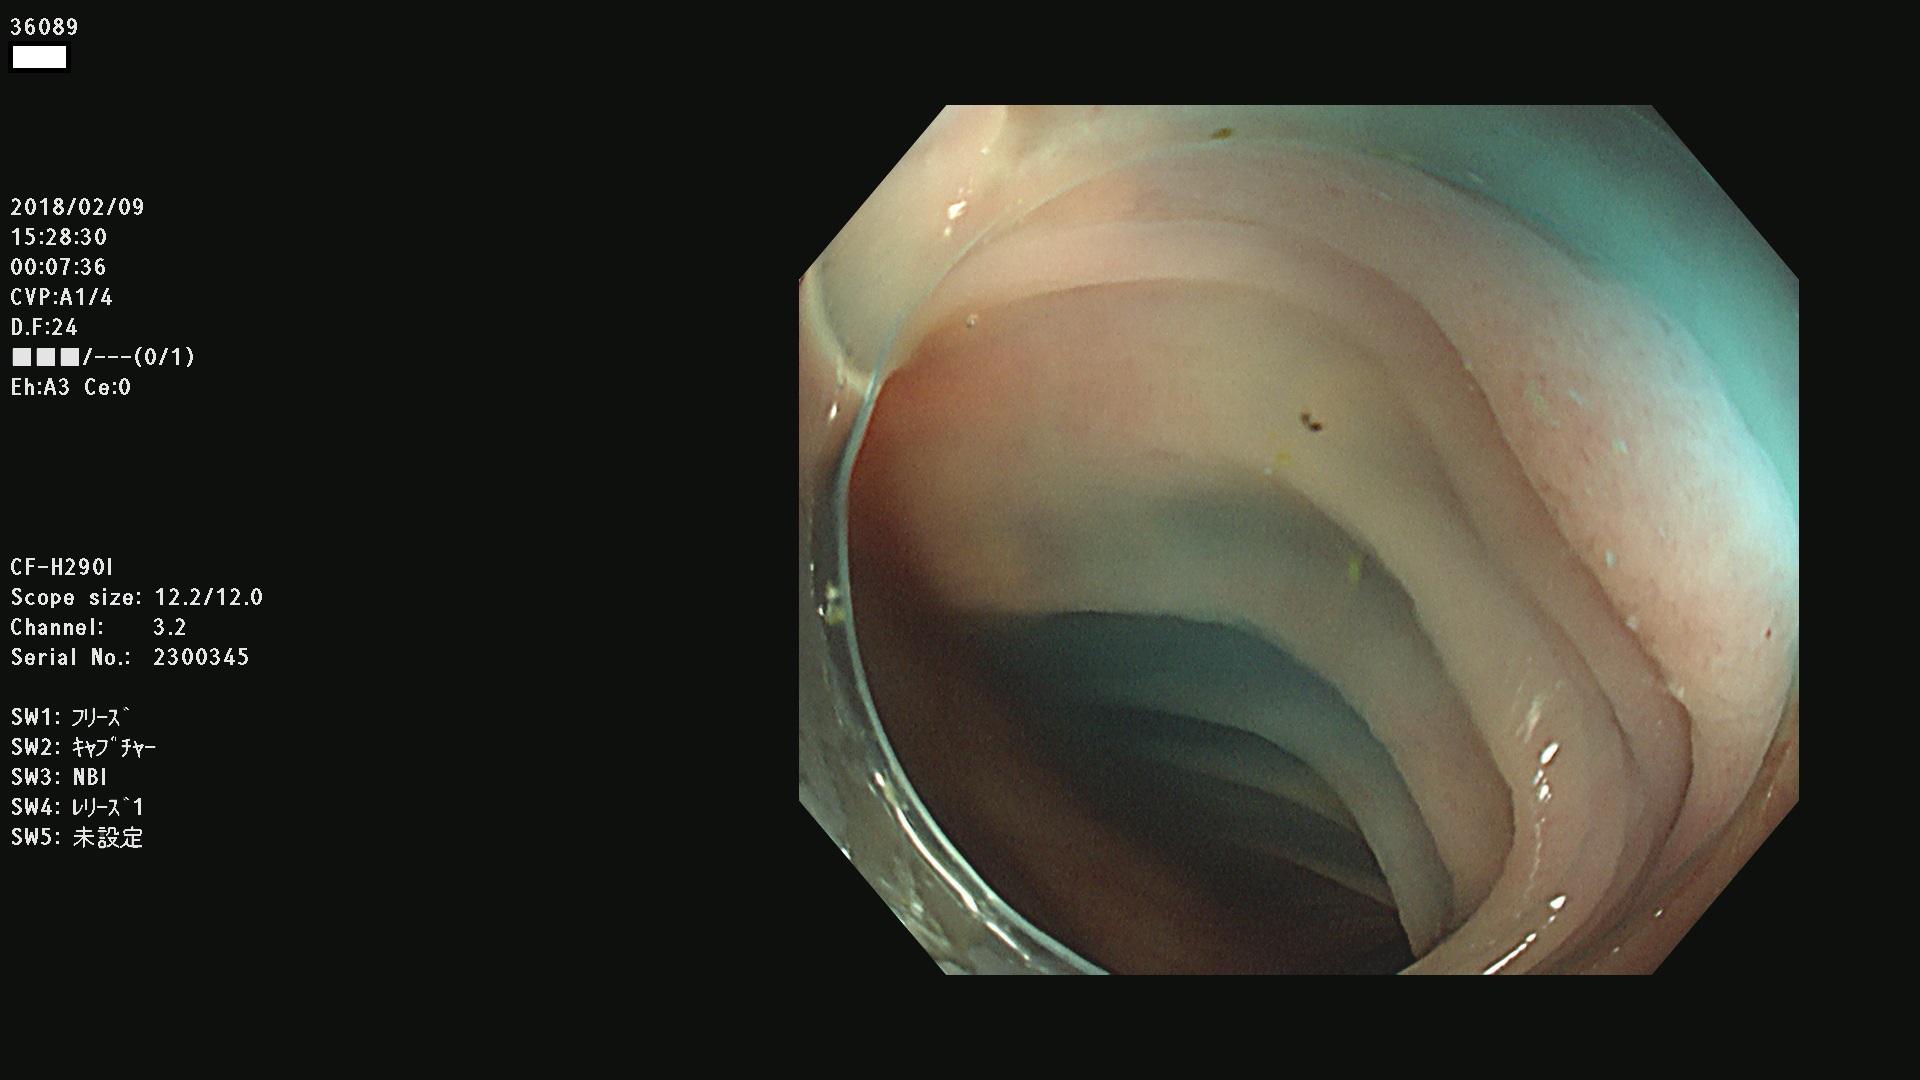

36000 36001 36003 36004 36008 36009 36012 36013(SSA/Pのみ) 36015 36016 36017 36021 36022 36023 36027 36030 36033(SSA/Pのみ) 36036 36037 36042 36044 36045 36046 36047 36051 36053 36054 36055 36056 36057 36058 36059 36060 36061 36062 36073(SSA/Pのみ) 36074 36075 36076 36078 36081 36082 36083 36089 36090(SSA/Pのみ) 36094 36096

発見困難で危険性の高い平坦型病変(上記100名より抽出)